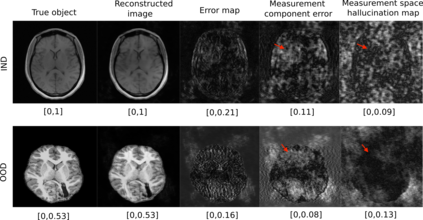

Tomographic image reconstruction is generally an ill-posed linear inverse problem. Such ill-posed inverse problems are typically regularized using prior knowledge of the sought-after object property. Recently, deep neural networks have been actively investigated for regularizing image reconstruction problems by learning a prior for the object properties from training images. However, an analysis of the prior information learned by these deep networks and their ability to generalize to data that may lie outside the training distribution is still being explored. An inaccurate prior might lead to false structures being hallucinated in the reconstructed image and that is a cause for serious concern in medical imaging. In this work, we propose to illustrate the effect of the prior imposed by a reconstruction method by decomposing the image estimate into generalized measurement and null components. The concept of a hallucination map is introduced for the general purpose of understanding the effect of the prior in regularized reconstruction methods. Numerical studies are conducted corresponding to a stylized tomographic imaging modality. The behavior of different reconstruction methods under the proposed formalism is discussed with the help of the numerical studies.

翻译:地形图象的重建一般是一个错误的线性反向问题,这种错误的反向问题通常利用事先对寻求的物体财产的了解加以规范化。最近,深神经网络通过从培训图像中学习物体属性的事先知识,积极调查使图像重建问题正规化;然而,对这些深网络所学的先前信息及其对可能存在于培训分发之外的数据进行概括化的能力的分析仍在探讨之中。以前不准确的情况可能导致在重建的图像中出现假结构,并引起医疗成像的严重关切。在这项工作中,我们提议通过将图像估计分解为一般测量和无效组成部分来说明重建方法以前强加的图象重建方法的效果。引入幻觉图的概念是为了了解在常规化的重建方法中以前的效果的一般目的。进行数量学研究时,与一种结构化的成像模式相对应。拟议形式下的不同重建方法的行为在数字研究的帮助下得到了讨论。